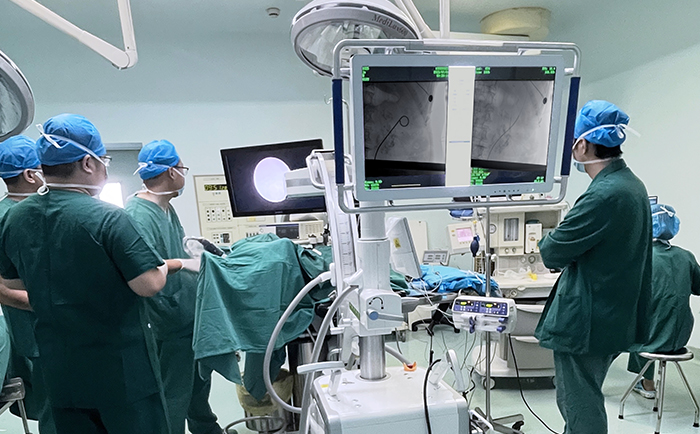

患者采用結石位進行該手術。全麻后,操作輸尿管鏡從尿道進入膀胱,通過鏡下觀察,找到輸尿管開口。此時,在普愛醫療大平板一體式C形臂透視引導下,穿入導絲,到達腎盂并確認位置,同時配合輸尿管鏡,找到狹窄部位。接下來,同樣在透視引導下,沿導絲插入雙J管支架,當支架兩端到達相應位置后,抽出導絲和輸尿管鏡,完成手術。

普愛醫療大平板一體式C形臂臨床圖像